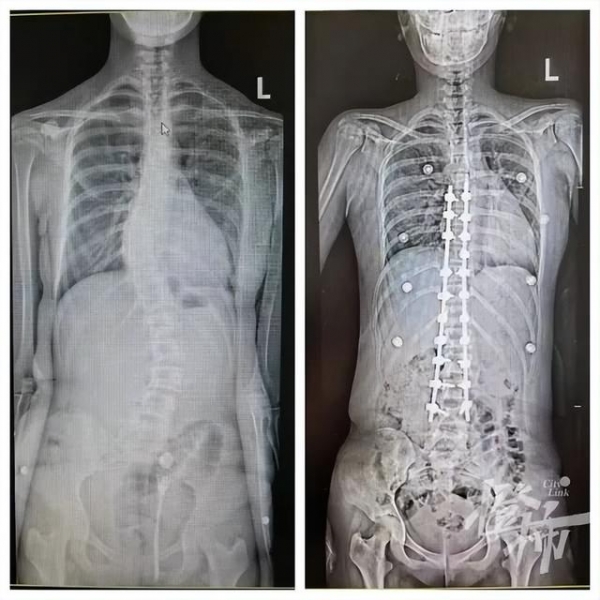

可可手术前后的对比图 医院供图

但好在最后可可的手术结果很不错,达到了预期效果。